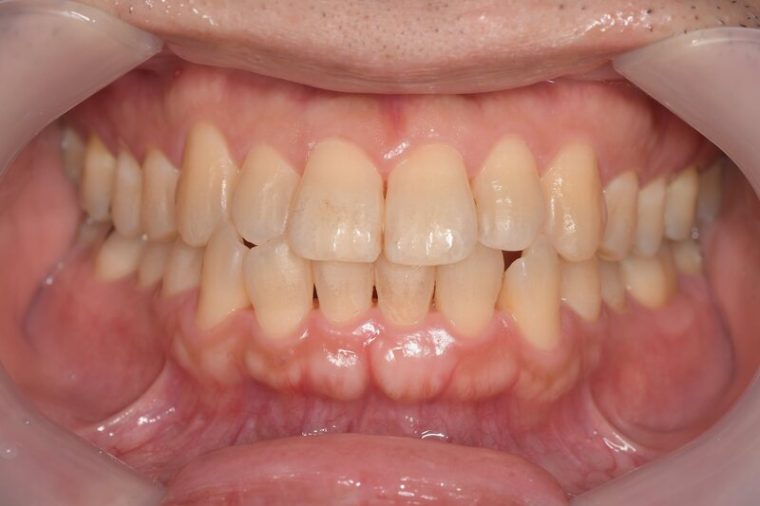

健康な歯ぐきの特徴

健康な歯ぐきは、綺麗なサーモンピンク色で、歯と歯の間が三角形でうまっています。近くで見ると、表面にみかんの皮のような細かなつぶつぶがあります。痛くない程度の力で歯ブラシの毛先を歯ぐきに当てて磨いてみましょう。出血が起こらなければ、健康な状態だといえます。

健康な状態の歯ぐきの写真